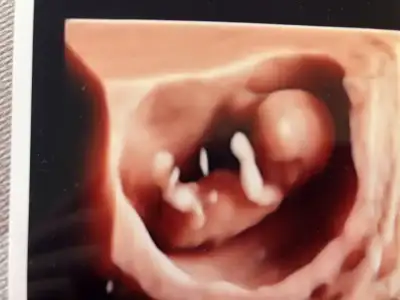

Merhaba ilki 9 haftalık son üçü 11 haftalık bir tahminde bulunabilir misiniz:)